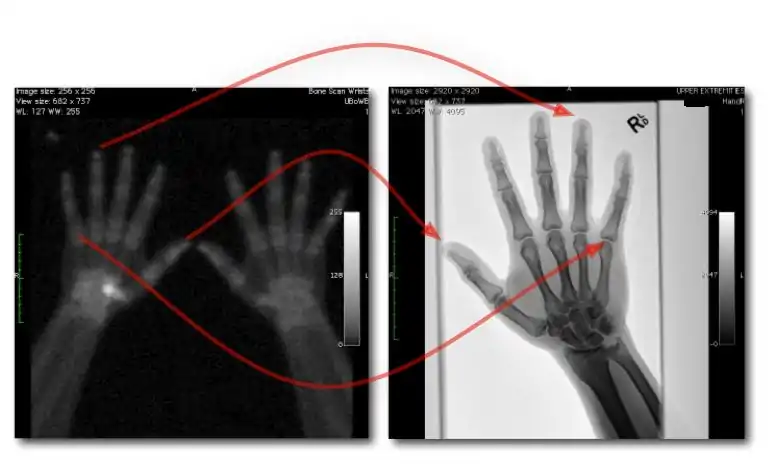

![]() Fig. 7.15.2: Effect of window width and level on CT image display: (a) Level = 50; Width = 200. (b) Level = 50; Width = 400. The image in (a) is displayed with greater contrast and appears noisier than that in (b). | ![]() Fig. 7.15.3: Effect of window width and level: (a) Level = -600; Width = 1700. (b) Level = -60; Width = 400. Image (a) displays the lung tissue more clearly, while image (b) can be used to highlight any pulmonary lesions. |

- Examples of image display manipulation are shown in the two figures above. In Figure 7.15.2, the same image of a slice through a patient's liver is displayed using a relatively narrow window (high contrast) and also with a wide window. The image with the narrower window appears noisier, but this is merely a reflection of the fact that the gray scale is spread over a narrow range of CT-numbers.

- Figure 7.15.3 illustrates the use of a relatively narrow window to highlight pathology in the lungs.